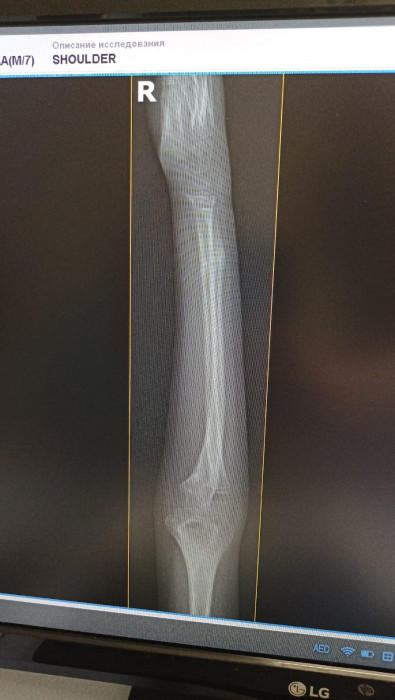

Кораблёв С.Г.: Да, вот ребёнок, 8 лет. Видно, перелом двух костей предплечья.

Кораблёв С.Г.: Адам, ещё раз: это второй снимок — боковая проекция. Это он на гипсе, это первичная репозиция, соответственно. И, вот, буквально они сделали на днях снимки, и всё прекрасно. Доктора сами удивились.

Кораблёв С.Г.: Я забыл сказать, что немного неправильно выбрали тип операции. Соответственно, здесь они поставили спицы, видите, но полностью сопостава не было. И там была еще ошибка, видимо, студенты удаляли, и после этого резко дёрнули, и перелом съехал в это положение. Это после операции. Они сказали: «Давайте подождем». И вот их выписали. Я смог забрать пациента себе, и вел на реабилитацию, поменял гипс, стянул, и мы каждый день работали-работали. И потом я с вашим методом познакомился.

Кораблёв С.Г.: Ну вот факт, такой есть факт. То есть здесь не просто перелом, то есть еще спицы сделали, он ходил с ними, сняли, съехало, и угловая деформация еще больше стала. И сейчас уже такой результат.